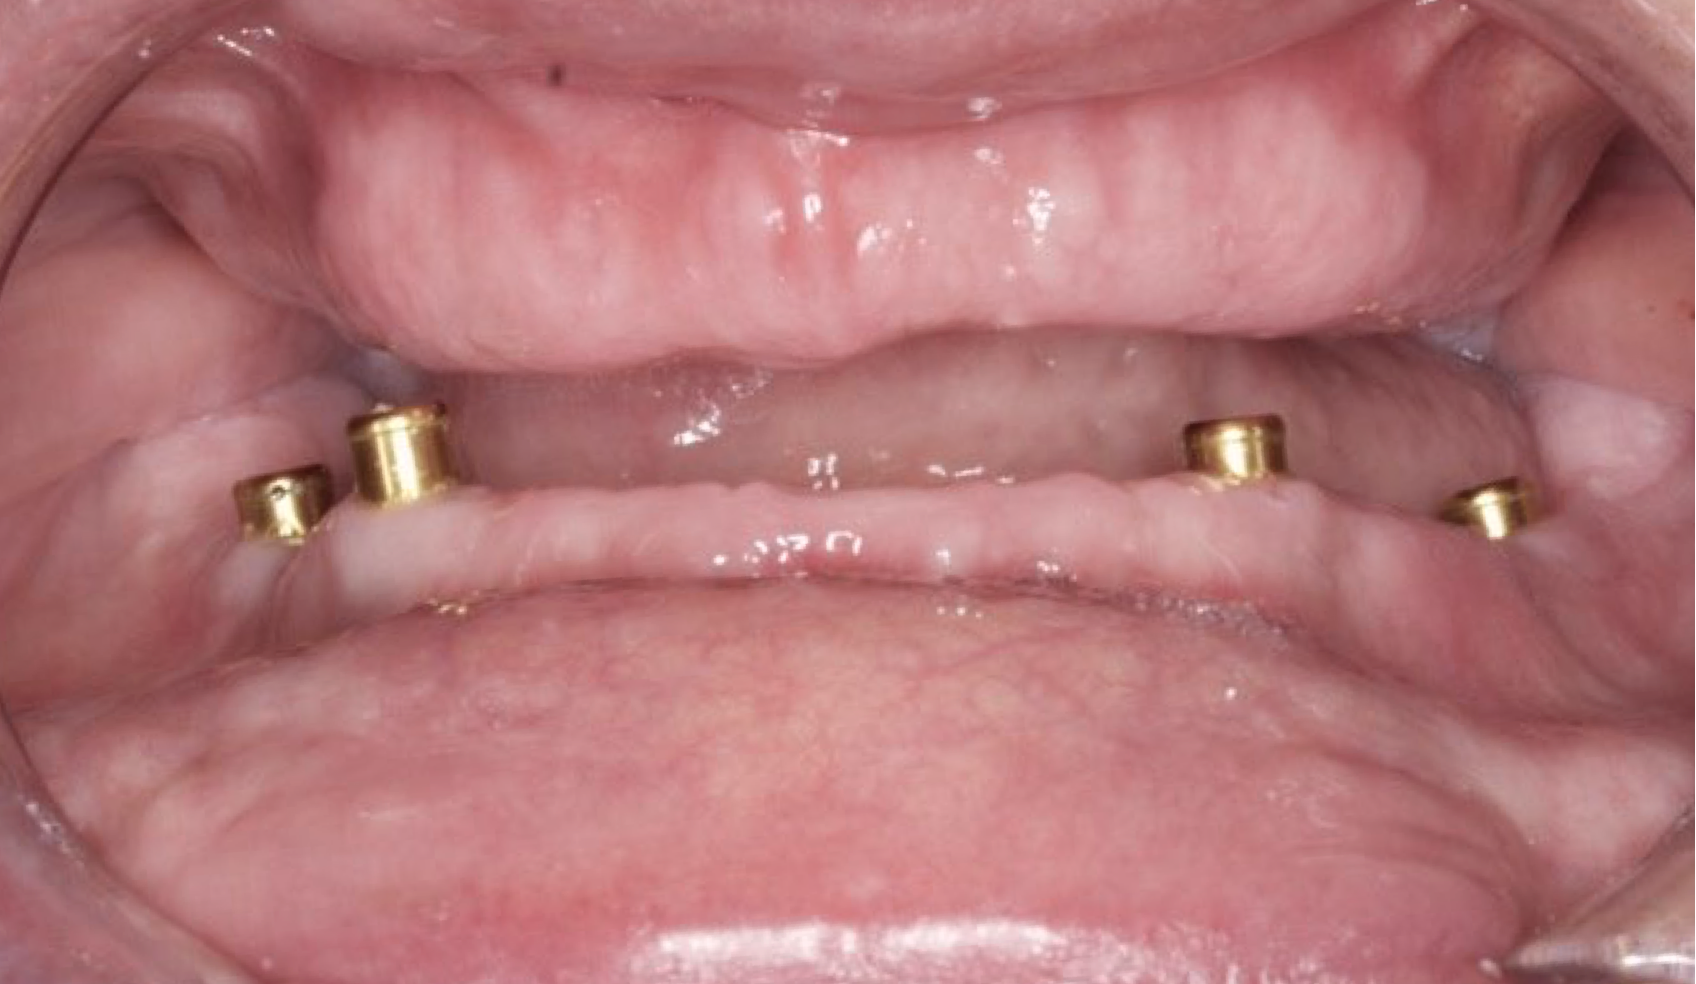

The patient had her implants placed 20 years ago. Four implants, particularly in the maxilla, were not positioned ideally for me to utilize and restore, while the four implants in the mandible were outdated and no longer functional. The patient's primary concern is to restore both function and aesthetics.

All on 6 for both arches Implants (#3,4,6,11,13,14,18,21,22,27,28,31)